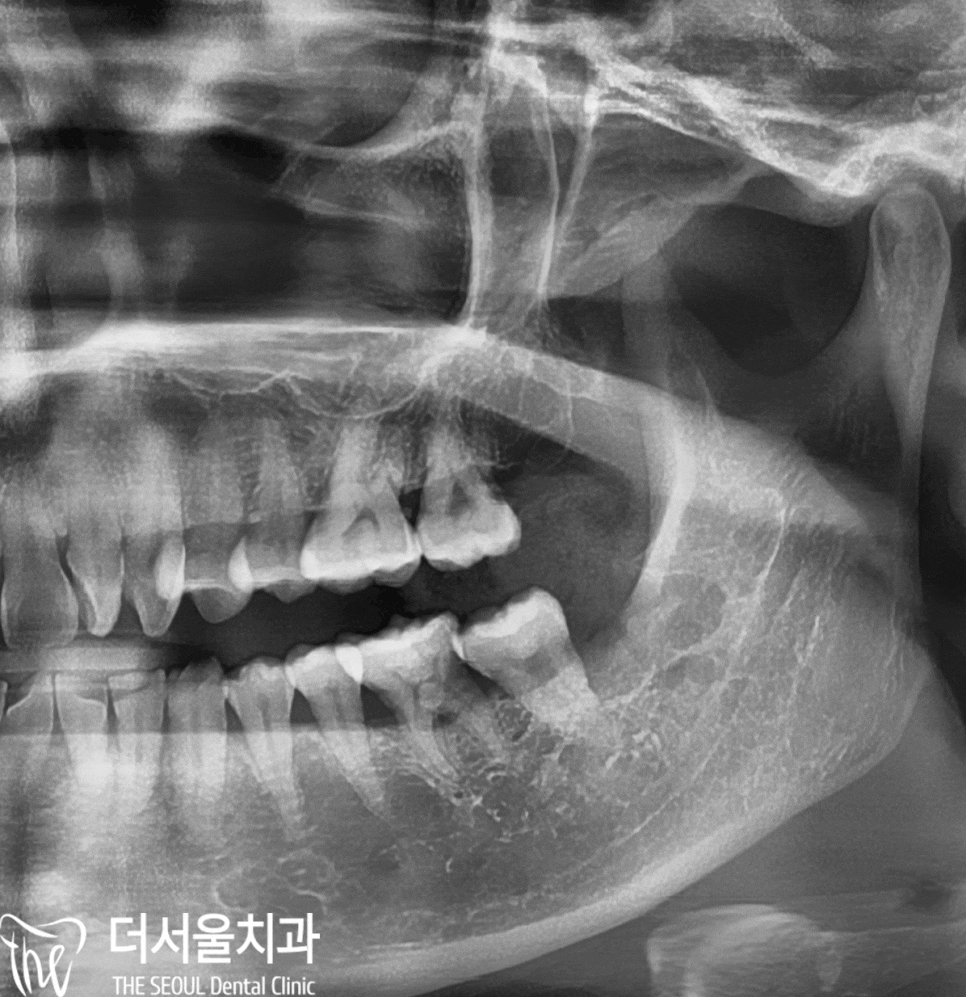

다행히 신경관과 떨어져 있었기 때문에

더 서울 치과 에서 사랑니 발치 를 하기로 했습니다.

그러나, 치아가 나올 공간이 부족했기 때문에

잇몸을 절개하고 나서

제3대구치를 작게 쪼개서 뽑아내게 되었습니다.